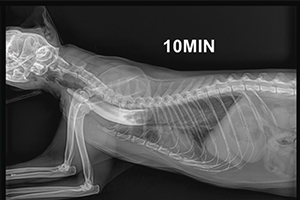

심장사상충 제거술 (Heartworm Removal) 중증 케이스

심장사상충 제거술은 중증 심장사상충 감염으로 인해 약물 치료만으로는 위험하거나 효과가 제한적인 경우 시행되는 중재적 시술입니다. 혈관 카테터를 이용해 심장 또는 폐동맥 내에 존재하는 사상충을 직접 제거함으로써 폐혈관 폐색과 급성 쇼크 위험을 줄이고, 심장 부담을 빠르게 완화하는 데 목적이 있습니다.

심장사상충 제거술 이미지 1

심장사상충 제거술

심장사상충 제거술 이미지 2

안내

환자의 상태와 심장·폐동맥 내 기생충의 위치에 따라 시술 난이도와 접근 방법이 달라질 수 있으며, 시술 전 정밀 영상 평가와 시술 후 모니터링이 필요합니다.